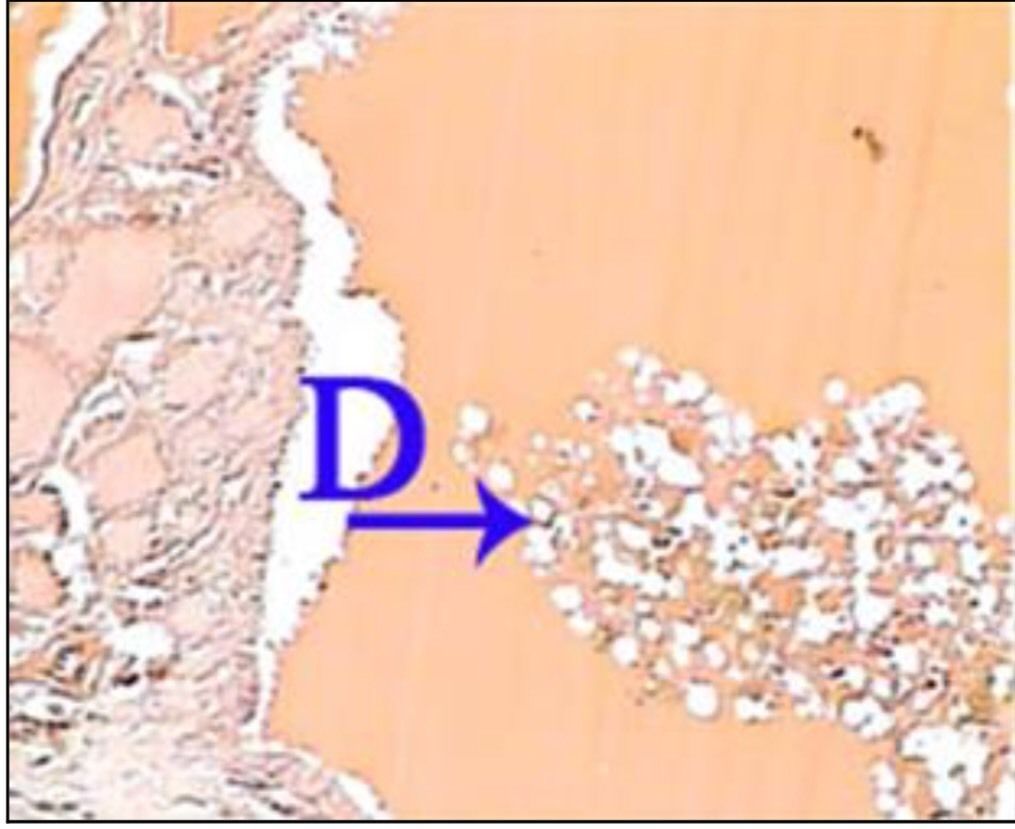

What is the correct answer at point D?

• - travées de sclérose annulaire

• - nodule cirrhotique, sans veine Centro lobulaire

• - néoformation canalicule biliaire

• - infiltration lymphocytaire

• - hépatocyte contenant de la bile